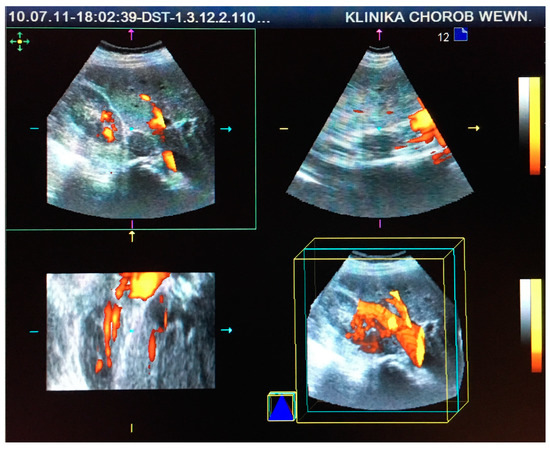

This retrospective study comprised 85 patients (71 women and 14 men) aged 30–81 (mean age 61 ± 16 years), who were hospitalized at the Department of Internal Medicine and Oncological Chemotherapy due to incidentally detected adrenal tumors in 2010 and 2011. Each patient underwent CT or MRI scans and US examinations before and after intravenous administration of SonoVue contrast (Bracco International B.V., Amsterdam, Netherlands) in two-dimensional (2D) and three-dimensional (3D) projections using Doppler techniques, as seen in Figure 1 and Figure 2. CT/MRI and US/CEUS examinations were performed at intervals of up to 6 weeks. US scanning was performed by a certified US specialist using a Siemens Acuson Antares instrument (Siemens Medical Solutions USA, Inc. Mountain View, CA 94043, USA) with a 2–6 MHz convex transducer. Based on the performed imaging, hormonal tests, and pathological evaluation of oligobiopsy, 81 incidentalomas, 2 pheochromocytomas, 1 case of adrenocortical carcinoma, and 1 liver cyst were diagnosed.

Figure 2. Visualization and vascularization analysis of the same adrenal tumor in contrast-enhanced ultrasound (CEUS) using power Doppler and three-dimensional (3D) techniques.